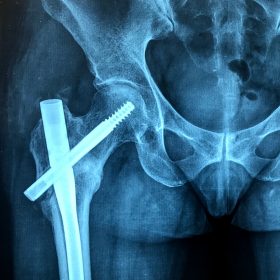

Υποκεφαλικό : Είναι ενδαρθρικό κάταγμα στον αυχένα του μηριαίου (το εσωτερικό του αρθρικού θυλάκου), το οποίο διακόπτει την αιμάτωση της κεφαλής του μηριαίου και οδηγεί σε μη πόρωση του κατάγματος (ΟΣΤΕΟΝΕΚΡΩΣΗ της Μηριαίας κεφαλής). Σε ασθενείς κάτω των 65 ετών αντιμετωπίζεται χειρουργικά με κοχλίωση στις πρώτες 12 ώρες. Τρείς βίδες σε σχήμα Τ με την βοήθεια τηλεόρασης διαδερμικά χωρίς διάνοιξη. Σε ασθενείς από 65-75 ετών γίνεται ολική αρθροπλαστική και σε ασθενείς άνω των 75 ετών αλλάζεται μόνο η κεφαλή χωρίς την αλλαγή της κοτύλης. Ο ασθενής περπατάει άμεσα μετεγχειρητικά στις 5 ώρες και εξέρχεται από το νοσοκομείο σε 1 -2 ημέρες. Στην κοχλίωση μπορεί να εξέλθει και την ίδια ημέρα.